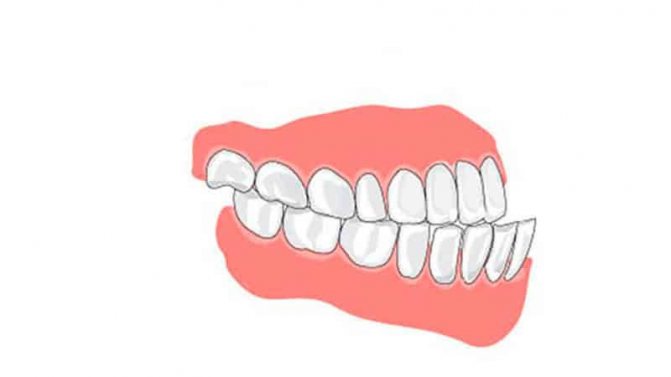

К аномальному расположению зубного ряда относят протрузию – смещение ряда вперед относительно нормального положения и ретрузию отклонение передних зубов в оральную плоскость. Для устранения проблемы применяют дугу Энгля, реже используются специальные небные пластины с активными дугами.

Если разница превышает 2 мм, то дистальные поверхности будут в одной плоскости по вертикали. В случае превышения этим параметром 2 мм говорят о наличии дистальной ступеньки. Все это в итоге развивается в дистальную окклюзию или прогнатический прикус – вариант, при котором нижние коронки расположены позади верхних.

Второй класс по Энглю – дистальное смещение зубов: сдвинут первый моляр снизу. Внешний бугор верхней шестерки со стороны щеки стоит на таком же бугре нижнего антагониста или заходит между зубных единиц №5 и №6. Патологически измененные положения касаются зубов всей челюстной дуги.